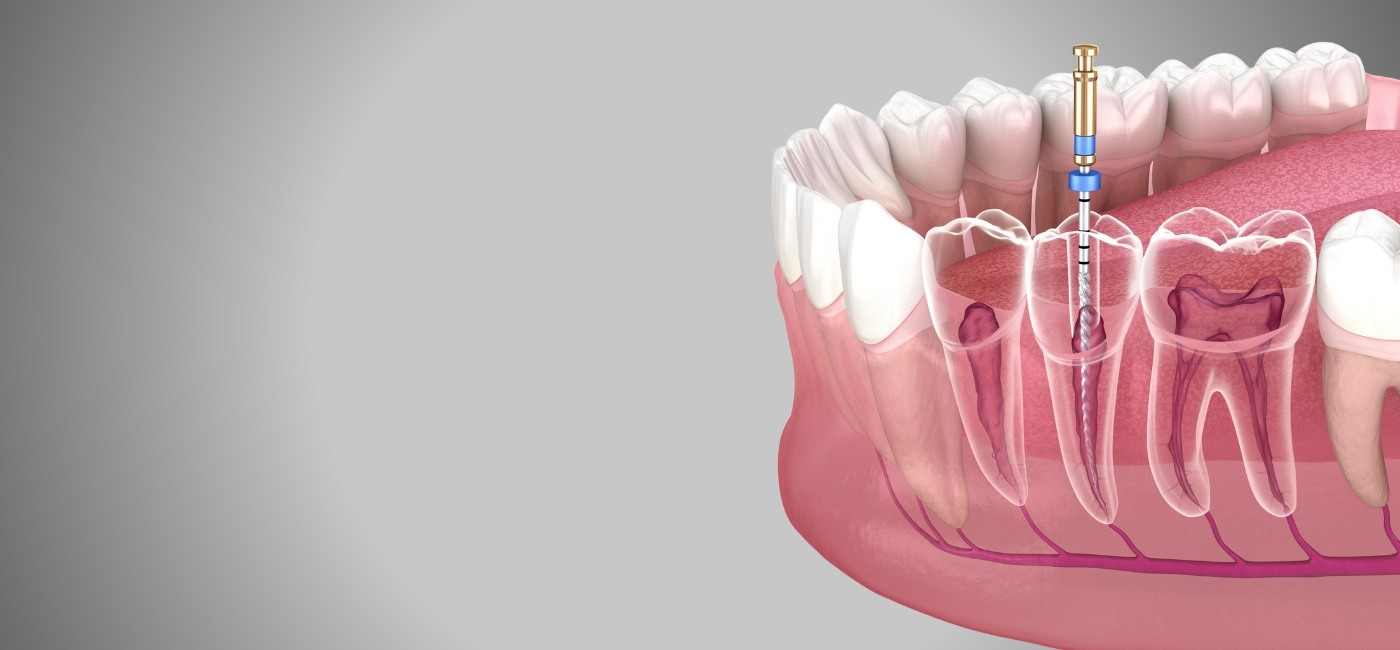

Complex Treatments made more comfortable

The focus is to give comfort at every step, from dental treatments to complex dental procedures, we follow the treatment accordingly.